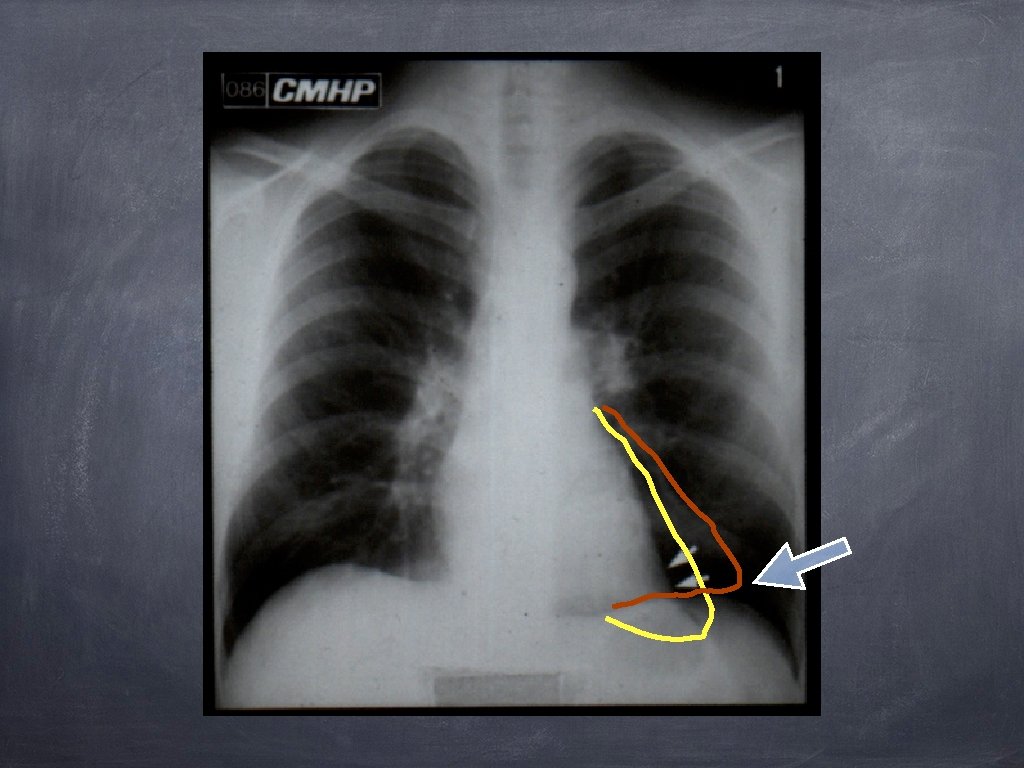

CARACTERELE GENERALE OPACITAȚILOR MEDIASTINALE LIMITA EXTERNA NETĂ ȘI CONTINUĂ FORMA CONVEXĂ SPRE PLAM N RACORD ÎN PANTĂ LINĂ CU MEDIASTINUL LIMITA INTERNĂ NEDELIMITABILĂ (SILUETAJ)

Semiologia opacităților mediastinale DEPLASĂRI ALE LINIILOR MEDIASTINALE; SEMNUL SILUETEI; SEMNUL CERVICO-TORACIC; SEMNUL CONVERGENȚEI HILULUI; SEMNUL ACOPERIRII HILULUI; SEMNUL “ICEBERG” – ului; SEMNUL ATRACȚIEI ESOFAGULUI